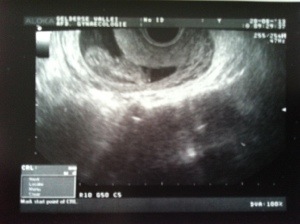

En dit is mijn broertje of zusje:

En nu van voor: